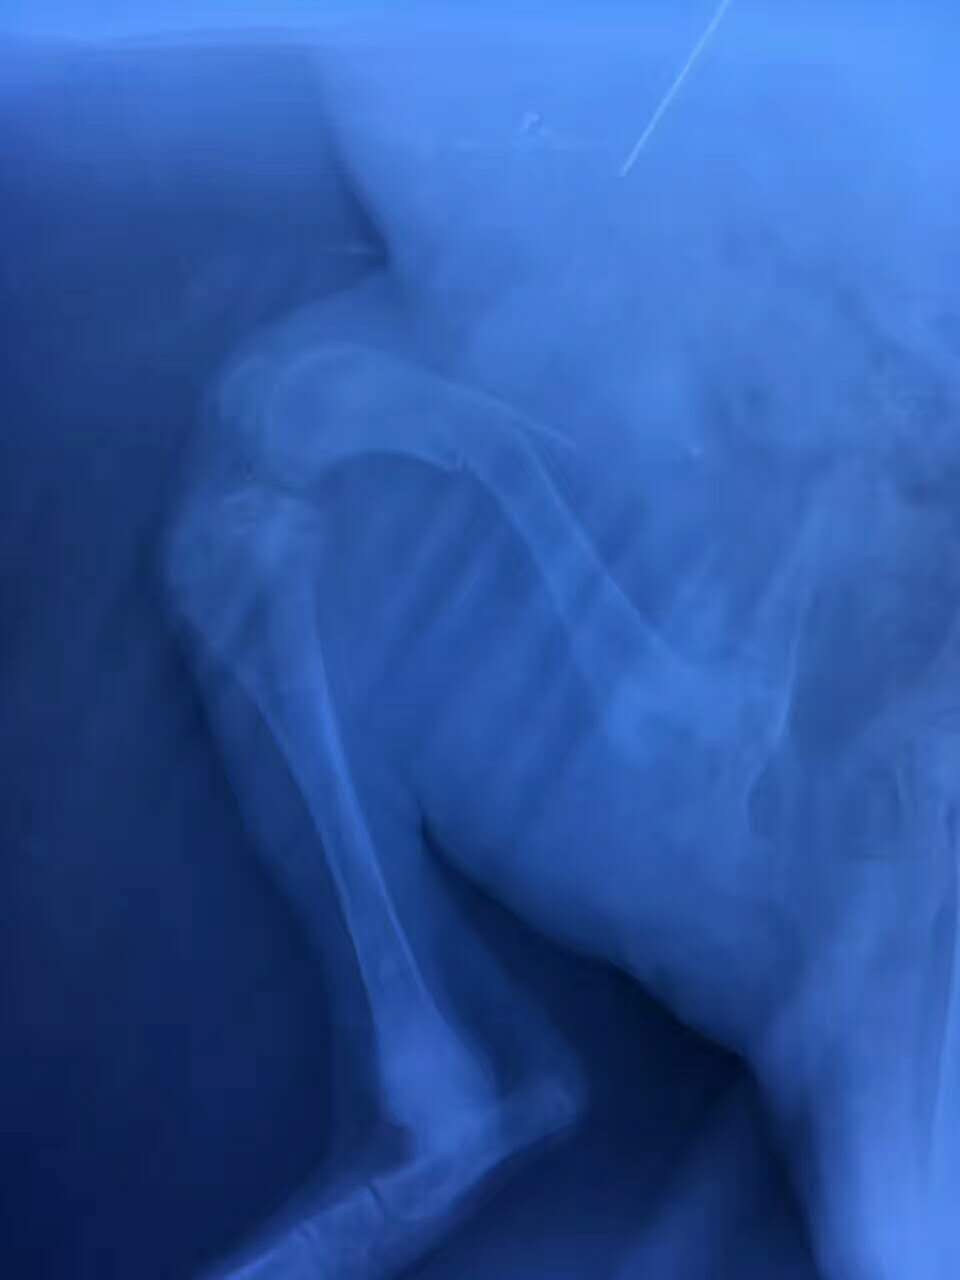

右后肢股骨骨干遠(yuǎn)端骨折手術(shù)

哈士奇骨折夜診:哈士奇 哈哈,從約1米高處跌落,致右后肢股骨骨干偏遠(yuǎn)端骨折,主人連夜送醫(yī),醫(yī)院當(dāng)晚手術(shù),手術(shù)非常順利,狗狗已蘇醒。我們的宗旨是把寵物的健康和生命放在*位,真正24小時接診,洛陽狗博仕寵物醫(yī)院。